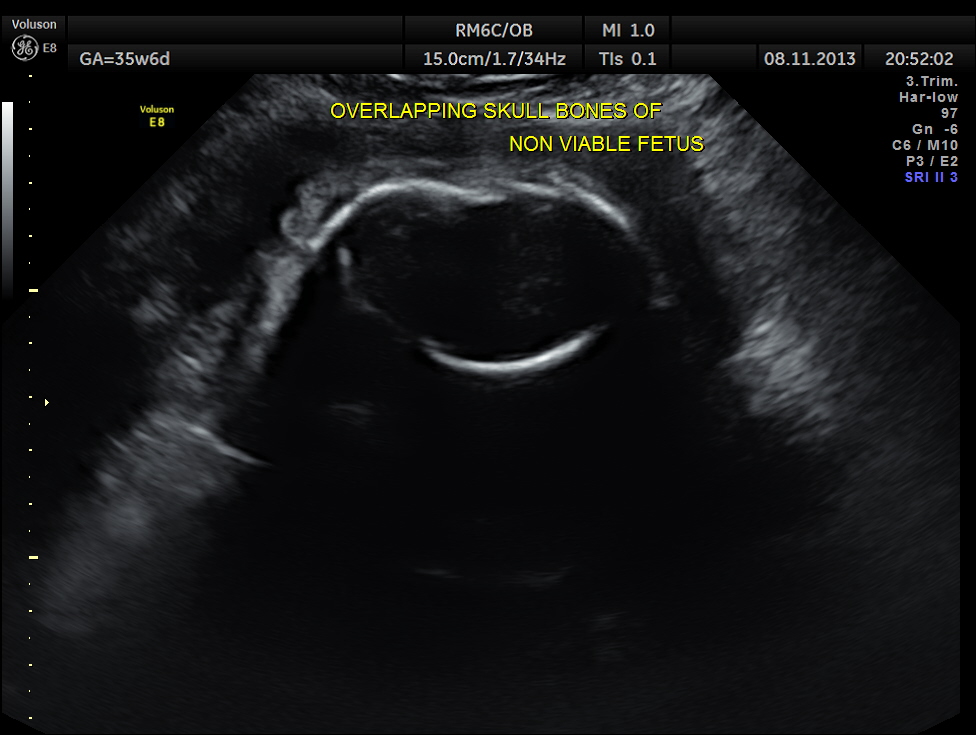

Intra uterine fetal death of the 2nd fetus was seen – Overlapping skull bones and maceration of fetal parts, with absent cardiac activity.

The overlapping skull bones of the fetus ,which died earlier .

Of twins, one showed intra-uterine foetal death and the other foetus probably had microcephaly.